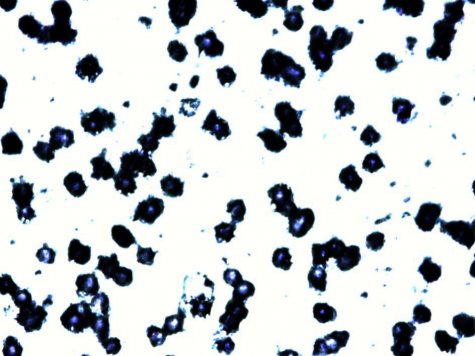

小分子果胶联合5-Fu、顺铂、紫杉醇等抗肿瘤药对MDA-MB-231细胞的抑制率明显增

加。具体见图2、3、4.

图2:小分子果胶、5-FU及联合用药对MDA-MB-231细胞抑制率的影响

图3 小分子果胶、顺铂及联合用药对MDA-MB-231细胞抑制率的影响

图4 小分子果胶、紫杉醇及联合用药对MDA-MB-231细胞抑制率的影响